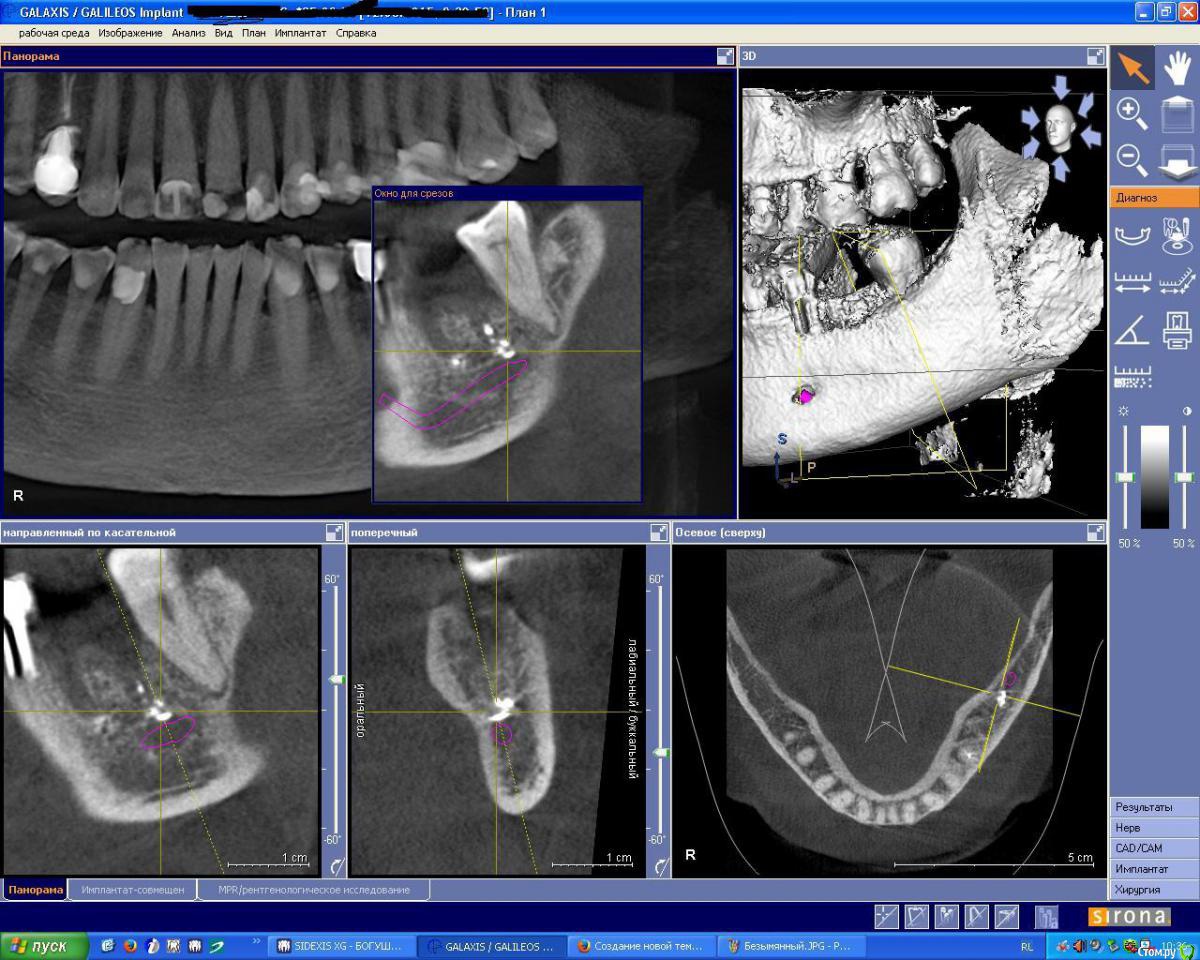

IshIm0 Опубликовано 12 августа, 2015 Поделиться Опубликовано 12 августа, 2015 (изменено) Добрый день коллеги, помогите определиться с тактикой лечения пациента на имплантацию. 18.04.15 Пациентке удалён зуб 36 с выпиливанием корней и полуторачасовым мучением - зуб буд-то анкилозировался с костью. Заживало всё не айс, сгусток вымылся, пища забивалась. Прошло 4 месяца - в полости рта как ни странно все хорошо, лунка под плотной бледно-розовой слизистой, кость при пальпации плотная, широкая. Жалоб не предъявляет - говорит давай имплантат, настроена позитивно. Далее на КТ определяется оставшийся пломбировочный материал, в лунке дистального корня зуба 36 пломбировочный материал лежит фактически на ничнежелюстном нерве. Планирую поставить ICX Ø 4,1 x 10mm, в межкорневую перегороду, уйти немного язычнее, но опасаюсь не даст ли мне этот пломбировочный материал воспалительную реакцию в последствии.Интересуют ваши мнения по поводу данной клинической картины!Позиционирование имплантата на КТ верно? (на КТ Astra 4.5 х 9 mm) Изменено 12 августа, 2015 пользователем IshIm0 Ссылка на комментарий